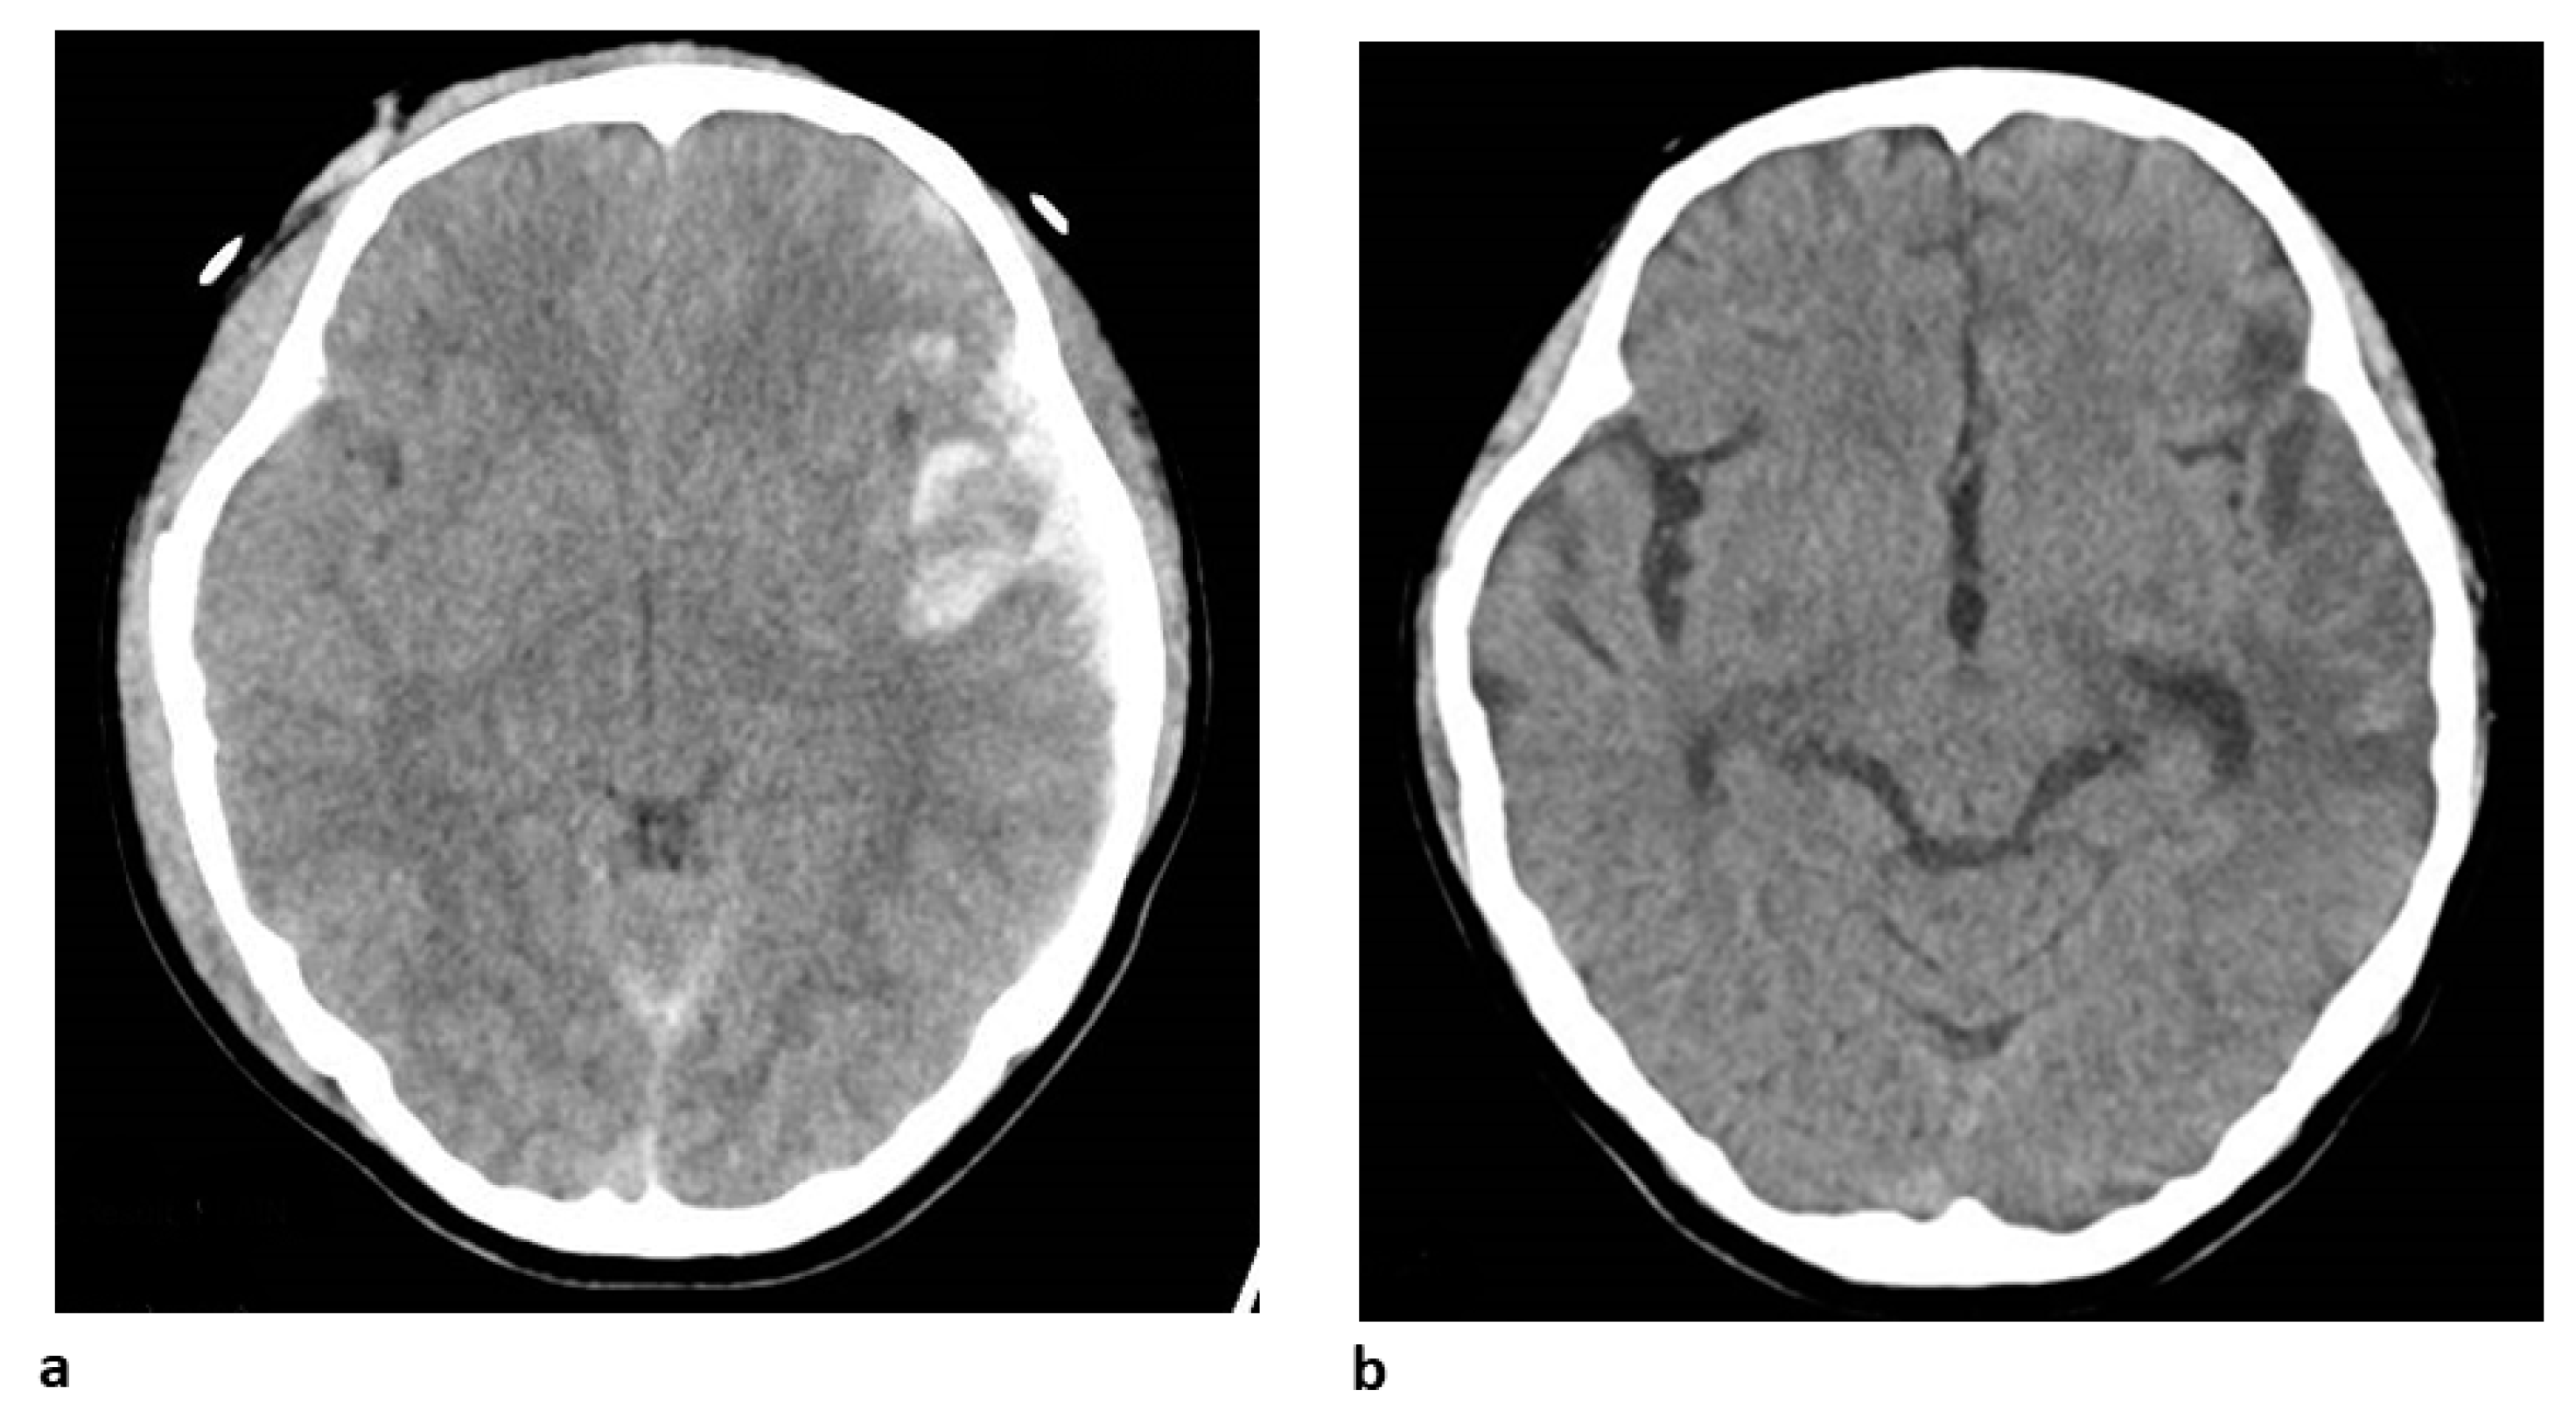

4. Clinical Case